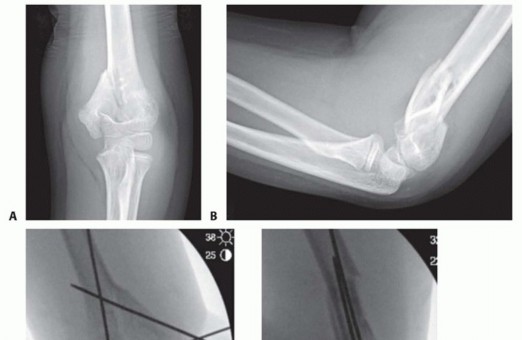

12 MIN READ Closed Reduction and Percutaneous Pinning of Supracondylar Fractures of the Humerus يناير 2023 Read More